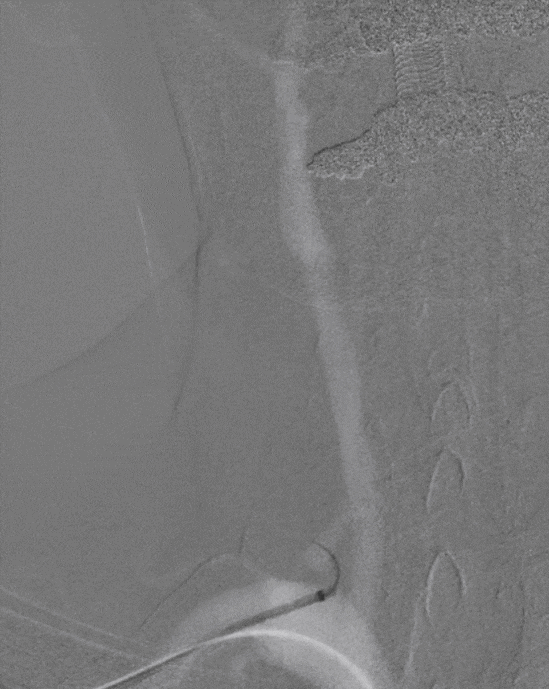

通桥白驹®球囊(2.5*10),先远后近扩张。

球扩后,狭窄改善。